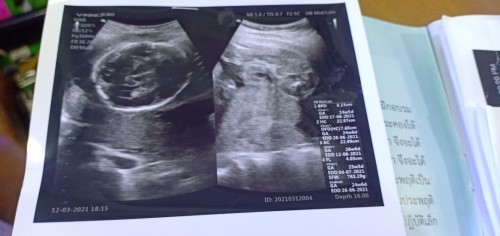

ฝากครั้งแรกตรวจเลือดพ่อ แม่ อัลตราซาวด์ 1 ครั้งตอน 4 เดือน ตรวจดาวน์ซินโดรม คิดว่าน่าจะได้อัลตราซาวด์ 2 ครั้ง ครั้งที่ 2 อาจจะใกล้คลอด เพราะแม่ปกติทุกอย่าง ตอนนี้ 5 เดือนแล้วค่ะ ☺️✌🏻ของบ้านนี้นะคะ ยังไม่ทราบเพศเลย ทำใจ 😂

ฝากครั้งแรกเจาะเลือดพ่อและแม่ ซาวตั้งแต่ครั้งแรกที่ไปฝาก เจาะเลือดตรวจดาวน์ซินโดรม แล้วก็ซาวให้ดูทุกครั้งที่หมอนัดเลยค่ะ ทราบเพศตอน 15 W หมอบอกละเอียดมากค่ะ

ฝากครรภ์ครั้งแรกได้เจาะเลือดพ่อกับแม่ค่ะ 16สัปดา ได้ตรวจดาวซินโดรมและซาวดูลูกเป็นครั้งแรก ตอนนี้26วีค หมอยังไม่ได้ส่งไปซาวอีกเลยค่ะ